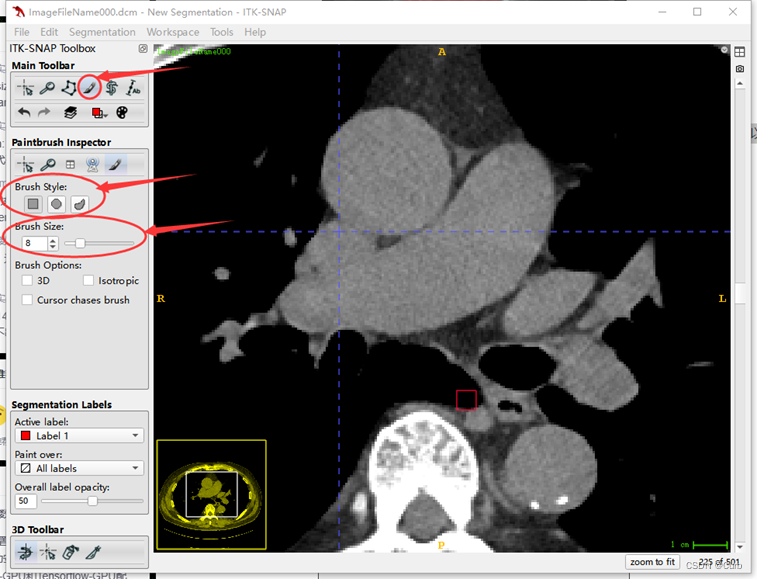

标注方法二:画笔标注

这里只进行简单介绍,流程和上面的套索标注差不多

在这一功能中可以使用类似画笔工具对标注的mask进行修改,在这个功能下鼠标左键是画笔,鼠标右键是橡皮。可以通过brush style和brush size调整笔头的形状和大小。